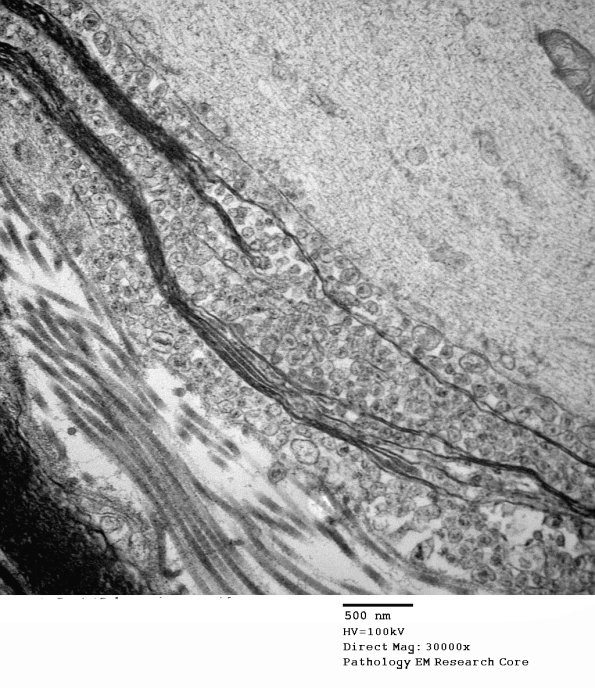

19C3 Artifact, vesicular myelin, spinal root EM 025A - Copy

Higher magnification of image #19C1. (electron micrograph)